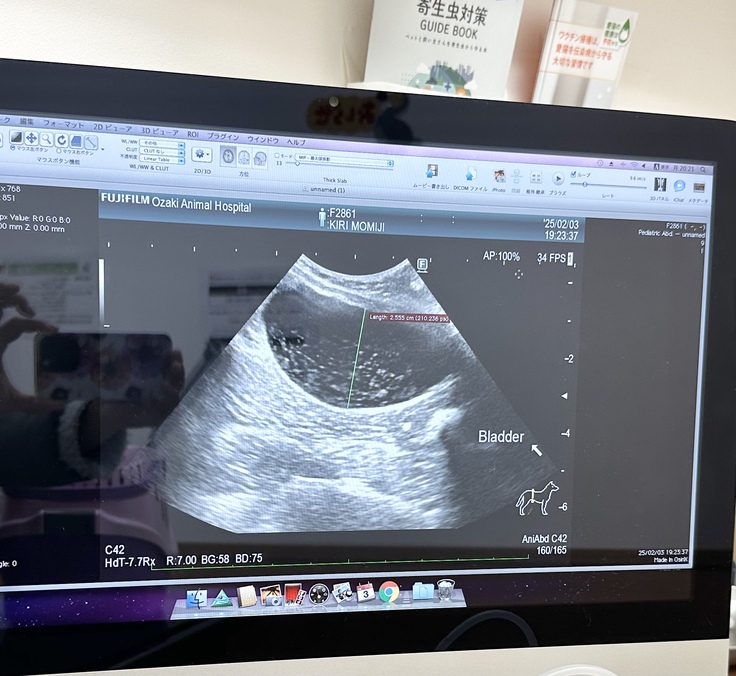

膀胱内は浮遊物が多く、血尿が貯留しているので結石があるのか判断できない状況でした。